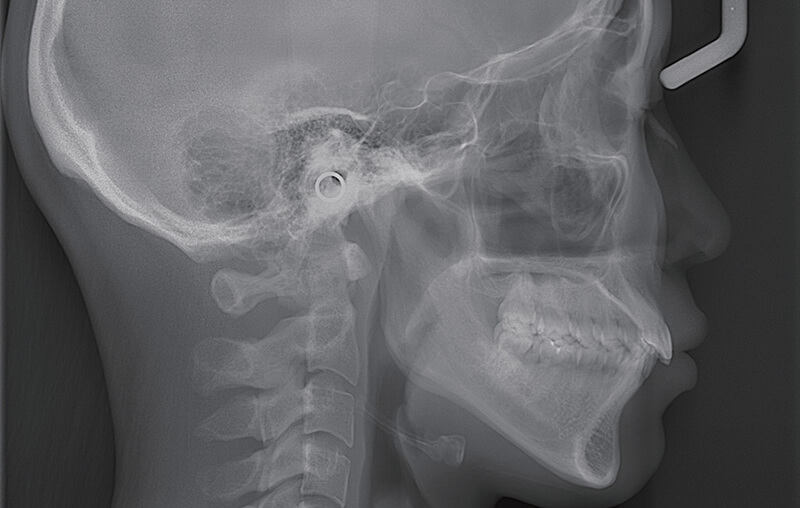

CTスキャン

CTスキャン:CTスキャンの導入によって、従来のレントゲンでは撮影できなかった「立体画像」の撮影が可能になりました。

より少ないX線照射線量で高画質画像が得られ、細かな形状までクリアに映し出すことが可能なので、より正確な診断が可能になり、インプラント手術をはじめ、様々な外科処置が必要な際、より確実で安全、安心な治療の提供が可能になりました。